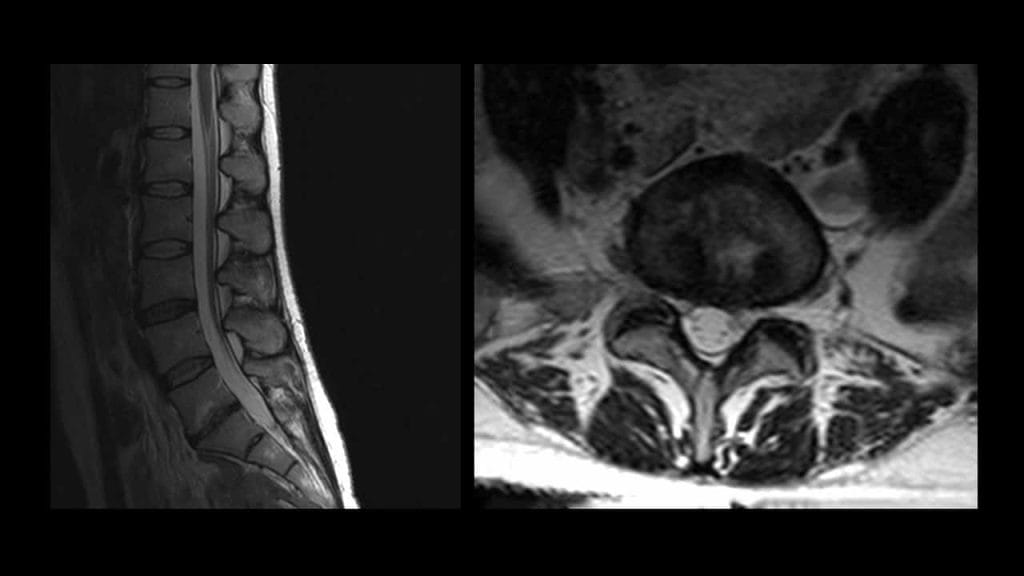

Features of Magnetic Resonance Imaging (MRI)

Magnetic resonance imaging (MRI) is a current technique to document the regression of herniated intervertebral disc fragments.

Several studies with lumbar MRI have demonstrated that the largest the lumbar disc herniations are most likely to show the greatest regression in size over time. Furthermore, disappearance of herniated disc material is seen frequently in the cases of migrating/sequestered disc herniation. Many studies have reported that the more the disc tissue migrated, the greater the subsequent decrease in size that could be observed.

Spontaneous regression time is not clear. It has been reported that the regression usually occurs between three months and one year.